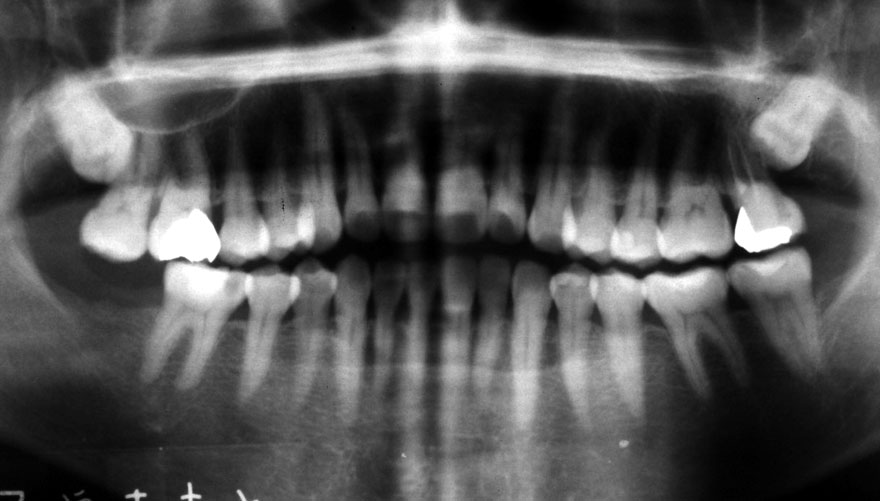

初診時 36歳 女性 平均歯槽骨喪失量:2.70mm

30年後 66歳

平均歯槽骨喪失量:3.26mm

30年間喪失量:-0.55mm

年間喪失速度:-0.018mm

(ケア頻度:3.01ヵ月ごと)